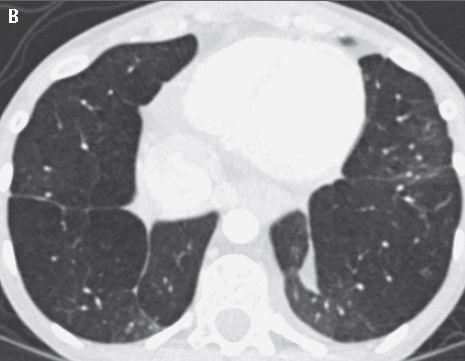

图2 胸部CT扫描图

Brent P. Little博士:胸部对比增强计算机断层扫描(CT)显示肺部过度充气,伴有严重的汇合性肺气肿和多发性肺大疱(图2A,2B和2C);支气管壁弥漫性增厚和出现含气薄壁囊腔,明显不存在支气管扩张。发现右上肺叶切除术后残端和动脉导管未闭的栓塞。主肺动脉扩张,直径3.8cm(图2D)。